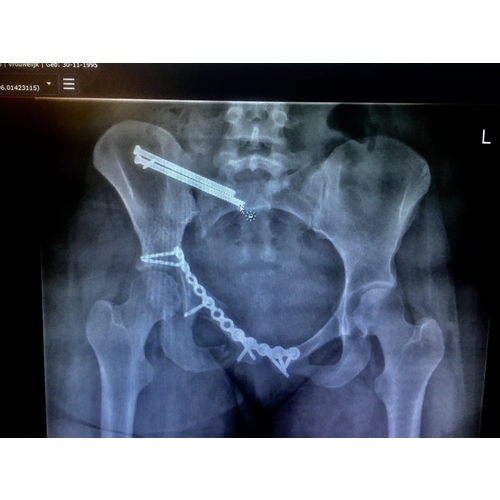

Vorig jaar mijn bekken op twee plekken gebroken en twee keer een operatie nodig gehad. En ongeveer een jaar later zwanger geworden van mijn eerste kindje. Het was in de eerste weken een gigantische hel qua pijn. Ik had al in de eerste weken bandenpijn wat gewoon voelde alsof er een miskraam zou gaan plaatsvinden. Bij traumatologie zeiden ze dat het na 8 weken minder zou worden en ze hadden gelijk. Met 7 weken een goede echo gehad. Nu ben ik 17 weken en tot zover gaat alles goed. Wel last van mijn bekken met opstaan etc maar het is te doen. Lopen zet ik nog wel op een laag pitje ivm overbelasting en verre afstanden (bijv. in het zkh) lopen doe ik niet. Dan zit ik in een rolstoel. Ze gaven wel al aan dat aan het eind ik meer moeite kan gaan krijgen met lopen. Maar ik ben er van overtuigd dat het goed gaat komen :)

(Op de foto zie je hoe mijn bekken er aan toe was na het uitbreken van het osteosynthesemateriaal. Gebeurde spontaan, kans hierop is ongeveer 10%. Kort erna werd ik weer geopereerd om alles weer op zijn plek te zetten. Dit was geen makkelijke klus zeiden ze. Maar alles is goed gekomen en ik ben nu zelfs zwanger! :))